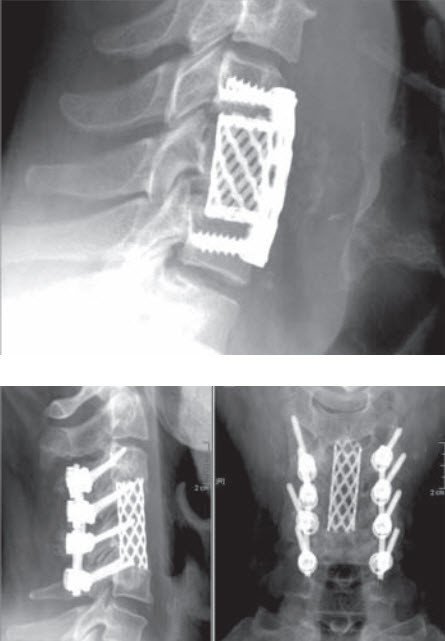

Ist bei der degenerativen Halswirbelsäule geplant, die Stellung der Halswirbelsäule zu korrigieren oder das Rückenmark zu entlasten, weil der Nervenkanal von vorne eingeengt ist, wird ein vorderer Zugang gewählt. Durch einen quer oder längs verlaufenden Hautschnitt kann dabei auf die Vorderseite der Halswirbelsäule eingegangen werden. Dadurch kommen die Vorderseiten der Wirbelkörper und die Bandscheiben ins Blickfeld. Je nach Eingriff wird hier die Bandscheibe isoliert oder zusammen mit dem Wirbelkörper entfernt. Dies ermöglicht den Zugang zum Nervenkanal. In dieser Phase muss besonders auf die Schonung des Rückenmarks geachtet werden.

Um Form und Stabilität der Halswirbelsäule zu erhalten, wird die Bandscheibe oder der Wirbelkörper ersetzt, und zwar mit geeigneten künstlichen Implantaten, Beckenknochen oder Knochenersatz. Sie haben die Funktion eines Platzhalters anstelle der entfernten Bandscheibe oder des Wirbelkörpers. Eine Plattenfixation kann erforderlich sein, wenn es darum geht, die Stabilität der Halswirbelsäule zusätzlich zu verbessern.

Als neuere Methode kann in gewissen Fällen die Bandscheibe mit einer beweglichen Prothese ersetzt werden. Damit wird eine Versteifung vermieden, und die potenzielle Überbelastung der angrenzenden Bandscheiben und Gelenke entfällt.